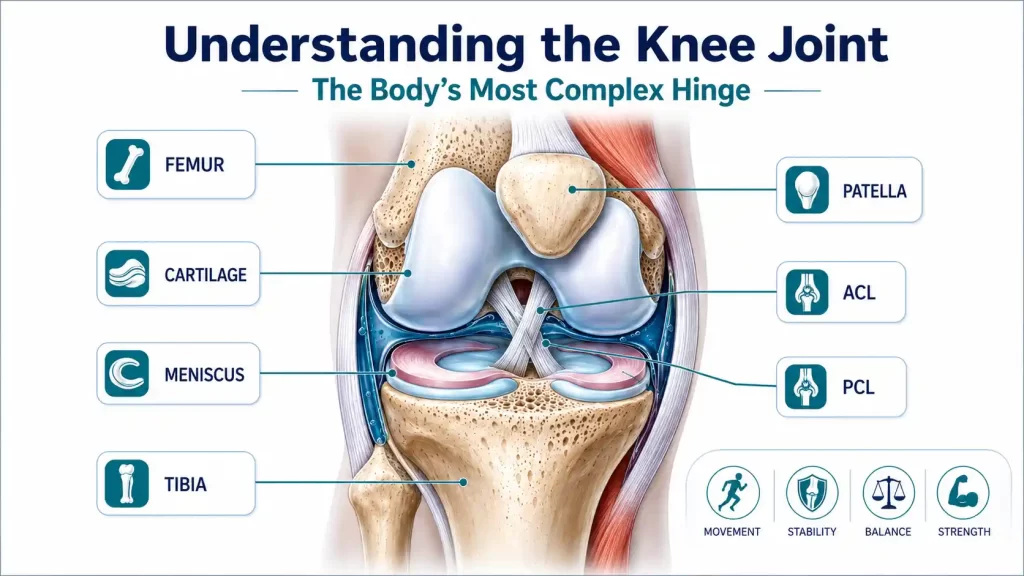

Think of your knee as the pivot of a suspension bridge: it bears the full weight of the body, absorbs ground-reaction forces during every step, and yet must rotate, flex, and straighten smoothly thousands of times a day. Unlike a simple door hinge, the knee combines three bones, four primary ligaments, two menisci, a bursa system, and the largest tendon in the body making it uniquely capable, and uniquely vulnerable.

The joint is formed where the femur (thigh bone) meets the tibia (shin bone), cushioned by the patella (kneecap). The joint surfaces are lined with hyaline cartilage a smooth, gel-like tissue that, once worn away, does not regenerate on its own. This is the root of most knee pain in adults.